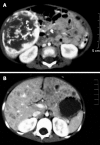

Results: The 12 patients were aged from fetal to 5 years (three males and nine females). The tumor was presented with different clinical manifestations, mainly as an asymptomatic, palpable, upper abdominal mass, except for the two fetuses who were detected antenatally by ultrasound. In one patient, this presentation was accompanied by an initial severe pneumothorax. No symptoms of congestive heart failure were present and neither congenital abnormalities nor vascular tumors in the skin or other organs were found. Laboratory abnormalities included leukocytosis (40%), anemia (60%), thrombocytosis (60%), hyperbilirubinemia (16.7%), abnormal liver function (50%) and increased α-fetoprotein (80%). Based on radiological findings and gross specimens, the tumor presented as a solitary lesion or a multifocal space-occupying lesion. The tumor size ranged from 5.0 cm × 3.5 cm × 2.0 cm to 13.8 cm × 9.0 cm × 7.7 cm, and the 0.2-1.1 cm nodules were diffusely distributed within the multifocal tumor. Seven cases were surgically resected, three cases underwent biopsy and the two fetuses were aborted. Histologically, nine cases were classified as type I and three as type II, presenting aggressive morphologic features, immature vessels, active mitosis and necrosis. An inflammatory component, predominantly eosinophilic granulocytes, sometimes obscured the nature of the tumor. Ten patients are alive after a follow-up of 1-9 years. Based on immunohistochemistry, the endothelial cells in all cases were positive for CD31, CD34 and polyclonal factor VIII antigen, whereas the scattered hyperplasia bile ducts were positive for cytokeratin 8 and cytokeratin 18.